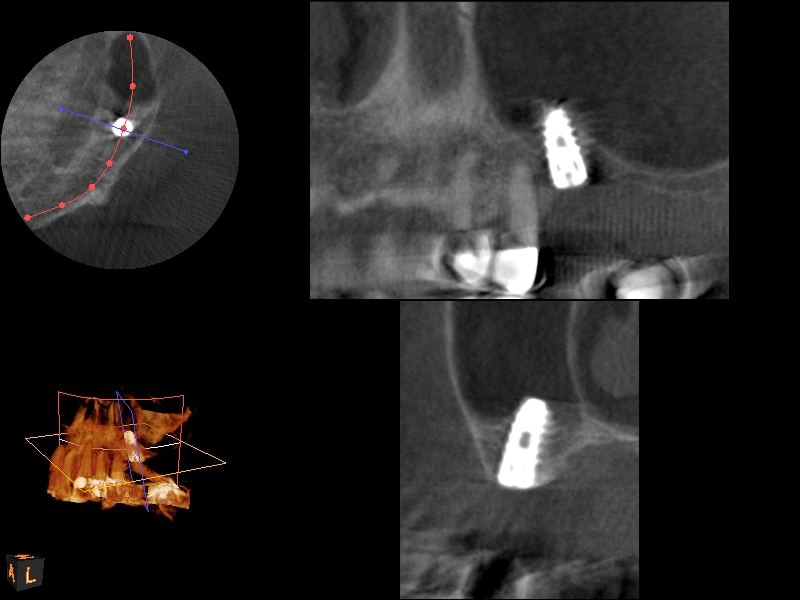

Fig. 21

CBCT scan (Kodak 9000D) of No. 3 area, day of placement. Appearance of native bone and bone graft is clearly discernable.

Fig. 22